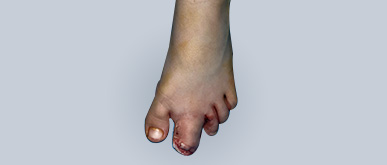

Çok Parmak (Polidaktili)

Polidaktili, elde normalden fazla parmak bulunmasıdır. En sık başparmak veya küçük parmak yanında görülür. Fazla parmak tam gelişmiş olabileceği gibi, küçük bir çıkıntı şeklinde de olabilir. Polidaktili, fonksiyonel olarak fazla sorun yaratmasa da estetik açıdan dikkat çeker ve aileleri endişelendirir.

Tedavide amaç normal el görünümü ve işlevi sağlamaktır. Bu nedenle fazla parmak cerrahi olarak çıkarılır. Ameliyat genellikle 1 yaş civarında planlanır. Bu yaşta çocuk güvenle genel anestezi alabilir. Cerrahi sonrası çocuklar ellerini normal şekilde kullanabilir, estetik görünüm de düzelir.